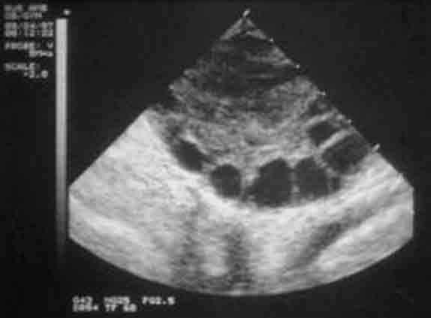

重慶送子鳥醫(yī)院表示,女性每個月經(jīng)周期開始就會有多個卵泡同時發(fā)育,但一般只有1個或2個卵泡發(fā)育至成熟,稱主卵泡(優(yōu)勢卵泡),其余卵泡它們就會相繼閉鎖。超聲在月經(jīng)周期第3-5天,可在卵巢內(nèi)發(fā)現(xiàn)小卵泡,以后逐漸長大,月經(jīng)周期的第7天,在被密集的發(fā)育卵泡群中,優(yōu)先脫穎而出發(fā)育成為優(yōu)勢卵泡。月在自然周期中,優(yōu)勢卵泡的生長速度先慢會快,卵泡直徑達18~28mm時稱為成熟卵泡。

成熟卵泡的B超表現(xiàn):

1、卵泡呈圓形或橢圓形,直徑達15-30mm(21.2+-0.53mm),卵泡內(nèi)呈無回聲區(qū),清亮純凈,邊界清晰,壁菲薄。

2、20%成熟卵泡在排卵前一天,可見卵丘圖像,在卵泡內(nèi)近壁處呈短強回聲。

通常每個周期B超監(jiān)測的次數(shù)應(yīng)控制在3~4次。監(jiān)測排卵應(yīng)該同時監(jiān)測內(nèi)膜厚度,以了解內(nèi)膜與卵巢平衡性及內(nèi)膜狀態(tài)。受孕時間的選擇,由醫(yī)生根據(jù)卵泡的大小及排卵時間指導(dǎo)同房的時間。